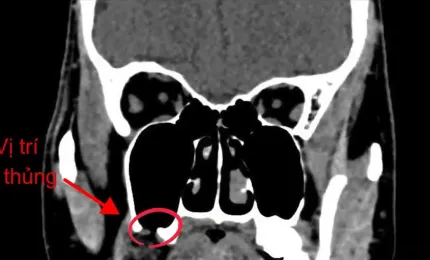

Ngạt mũi, đau đầu, thanh niên 25 tuổi nhập viện vì nhiễm trùng sọ

Trước khi nhập viện hai tuần, nam thanh niên 25 tuổi chỉ bị ngạt mũi, đau đầu nhẹ và được kê kháng sinh về uống.